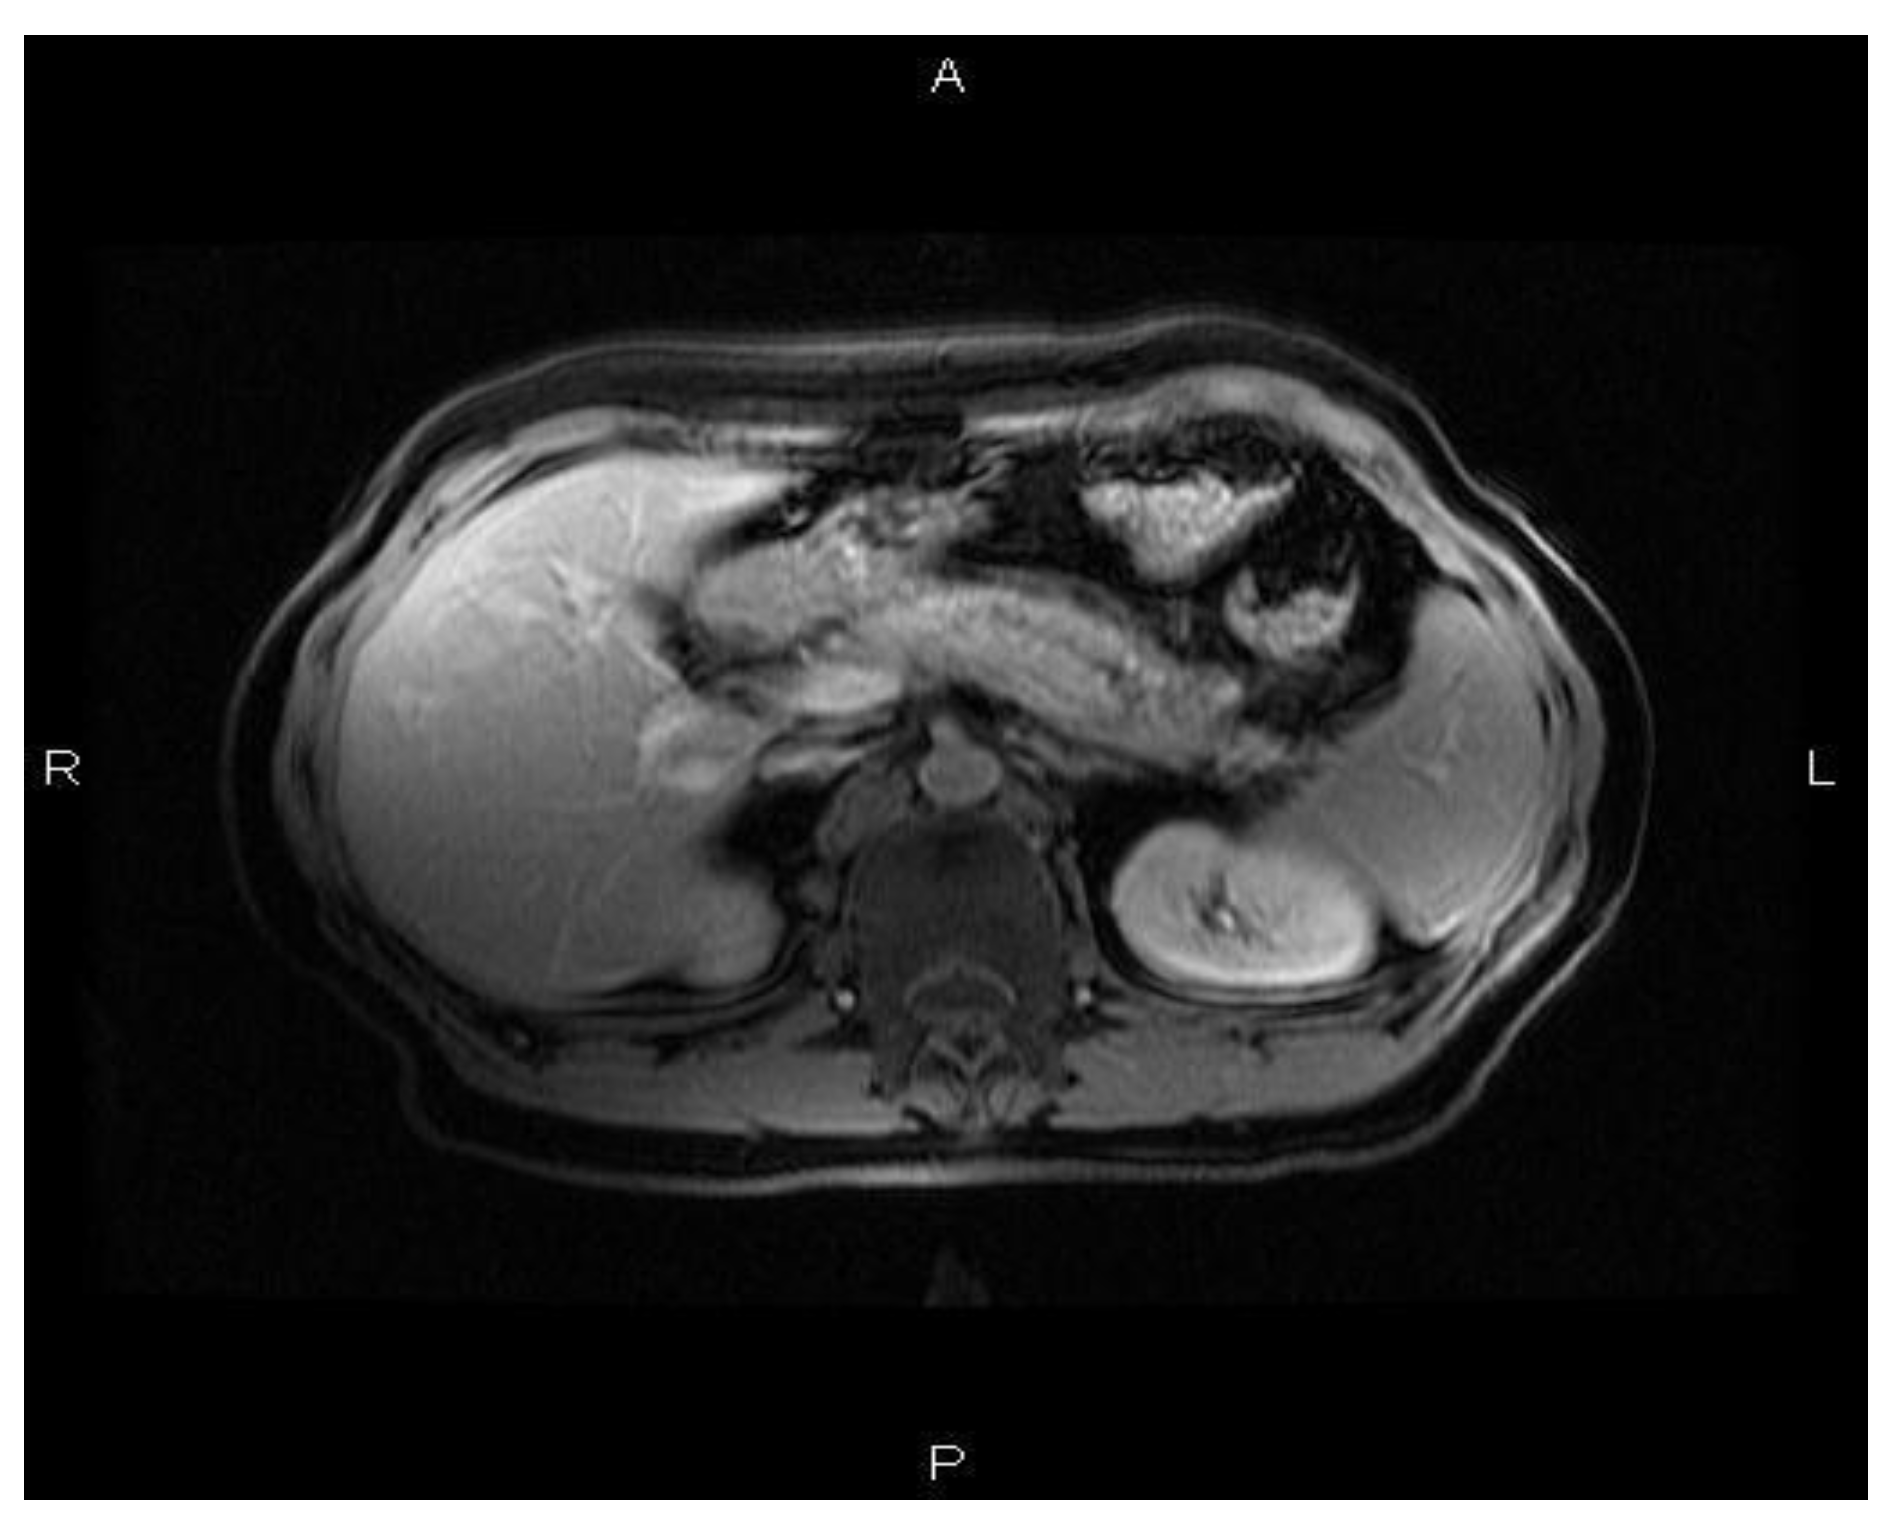

A 52-year old Caucasian man was diagnosed with chronic recurrent pancreatitis in 2007. The diagnosis was based on personal pathological history (repeated episodes of acute pancreatitis, biochemical, and imagistic investigations). A suggestive aspect of chronic pancreatitis evidenced by cholangio nuclear magnetic resonance is shown in Figure 1, Figure 2, Figure 3.

Figure 1. Axial T1 fat-supressed section: pancreas with mild enhancement, with discrete estompation of physiological peripheral lobulation associated with peripancreatic fat stranding and right dilatation of the Wirsung duct.